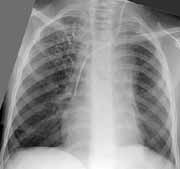

После предоперационной подготовки выполнена верхняя лобэктомия слева. Послеоперационный период протекал гладко. На контрольной рентгенограмме органов грудной клетки слева хорошее расправление легочной ткани. Через три недели произведена верхняя лобэктомия справа. Контрольное рентгенобследование также указывает на хорошее расправление остаточной легочной ткани справа.

Через 2 недели после второй операции пациентка выписана из клиники в удовлетворительном состоянии. С 1998 г. по 2000 г. состояние девочки остается достаточно хорошим. На серии контрольных рентгенограмм легочный рисунок не изменен, легочные поля чистые (Рис. 3).

Рис. 3. Почти полная нормализация рентгенкартины после лечения.